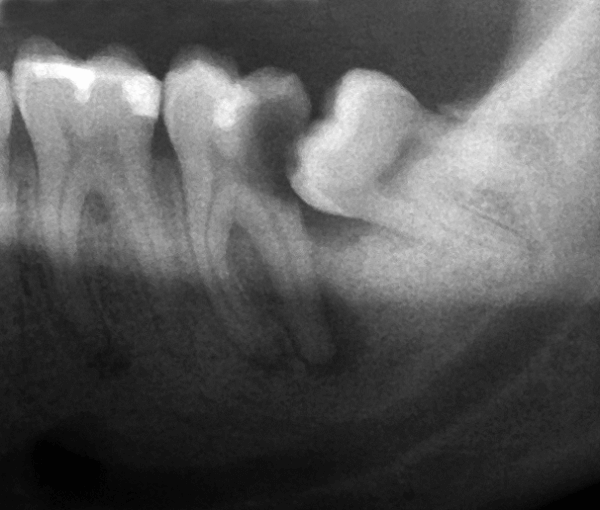

Periodontal Disease and Wisdom Teeth David C. Stahr, DDS Oral Surgery — Stahr Oral Surgery